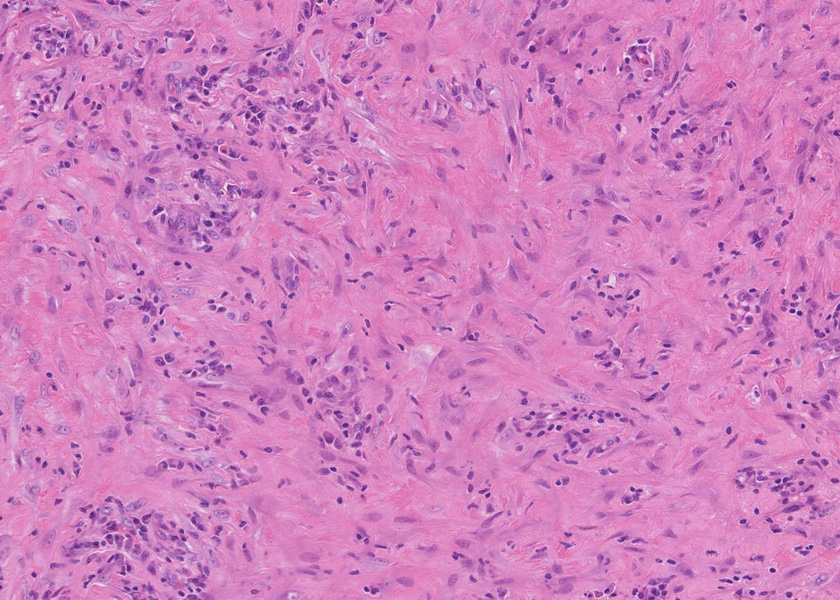

線維化組織に類円, 葉巻型淡明な核の紡錘型細胞が増生している。免染SMA陽性。血管周囲に慢性炎症あり。

組織像は膵腫瘤B, Cと同じくinflammatory myofibroblastic tumorである。島状に形質細胞主体の慢性炎症が強い。腹膜腫瘤には腺管は認められない。